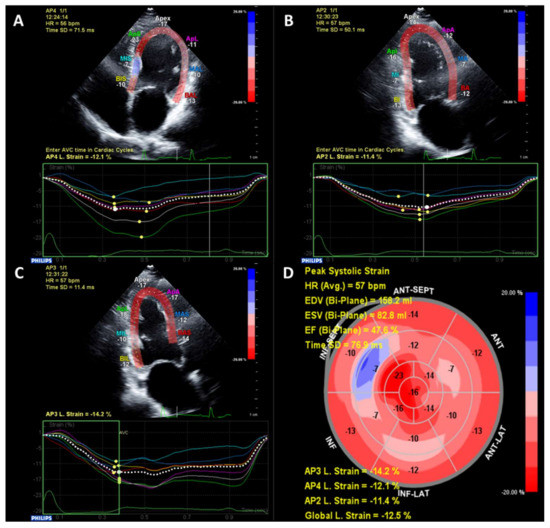

More recently, advanced echocardiography methods such as strain imaging using speckle-tracking have identified subclinical alterations in systolic myocardial function in patients with T2D and preserved LVEF (typically ≥50%) [22]. Strain is a measurement of myocardial deformation which is typically reported in three dimensions—longitudinal, circumferential and radial [23]. Strain is reported as a percentage change from diastole to systole, therefore due to the longitudinal and circumferential shortening of the myocardium lower values of longitudinal and circumferential strain represent better systolic function, whereas due to systolic myocardial thickening, higher values represent better systolic radial function. An example of strain imaging is shown in Figure 1. Global longitudinal strain (GLS) is the most studied parameter as it is more robust and reproducible, and also has independent, incremental risk prediction above and beyond ejection fraction [23,24]. GLS is frequently reduced even in T2D patients without overt structural heart disease compared to non-T2D patients [22]. Studies suggest that alterations in GLS may actually be a more sensitive marker of DCM than diastolic dysfunction [21].

Figure 1.

An example of echocardiographic speckle-tracking strain analysis. Images are taken in the apical 4-chamber (A), 2-chamber (B) and 3-chamber (C). A bullseye plot combining all three views is generated with reduced global longitudinal strain of −12.5% and reduced LVEF (47.6%) (D).